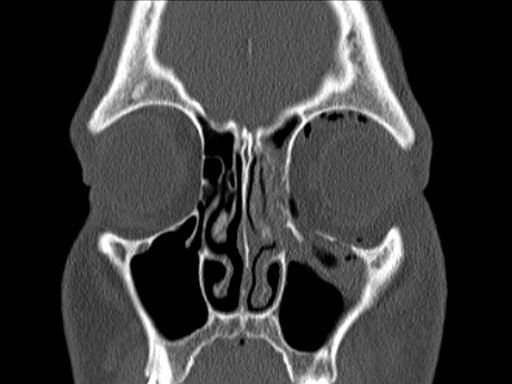

30-year-old male with fracture of left orbital floor and involvement of medial wall.

Case provided by Marc C Metzger, Freiburg, Germany

Fig 1 CT scan with fused image of virtual prebent orbital plate.